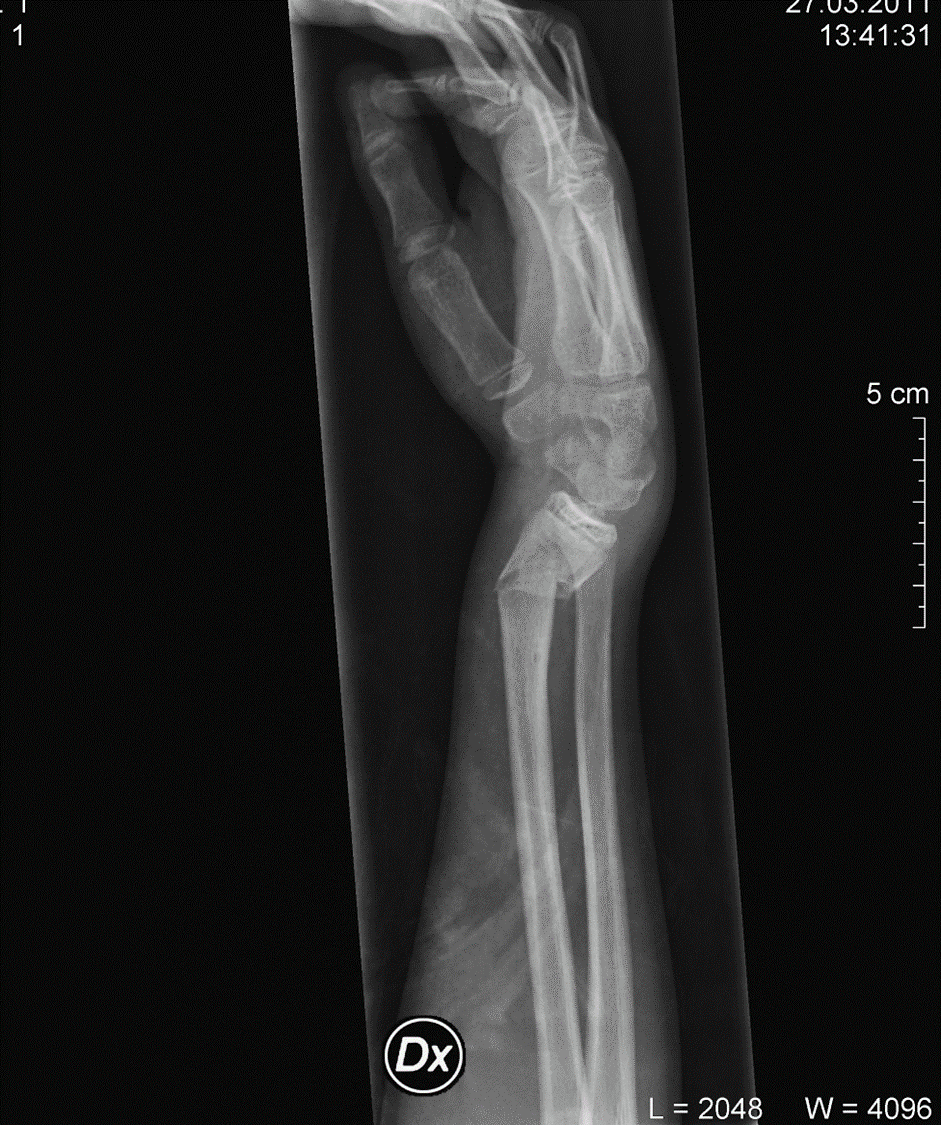

1) hvilke bruddskader som er blitt røntgenologisk påvist og behandlet i allmennpraksis i Bykle i perioden 2010-2014,

2) hvordan er pasientenes symptomer og funksjon etter konservativ bruddbehandling av de tre vanligste bruddlokalisasjonene (underarm/håndledd, kragebein, ankel) i allmennpraksis

Studie 1 er en retrospektiv tverrsnittstudie med utgangspunkt i alle brudd bekreftet av røntgenavdelingen ved Sørlandet Sykehus Arendal og behandling igangsatt i Bykle. Det ble registrert relevante journaldata og røntgenologiske data på alle pasienter som er diagnostisert med positivt røntgen på brudd fra 2010.

Studie 2 er en spørreskjemaundersøkelse som inkluderte alle pasienter med brudd i underarm/håndledd, kragebein og ankel for å registrere funksjon etter gjennomgått brudd og behandling. Det er også innhentet demografiske opplysninger om behandlende lege.